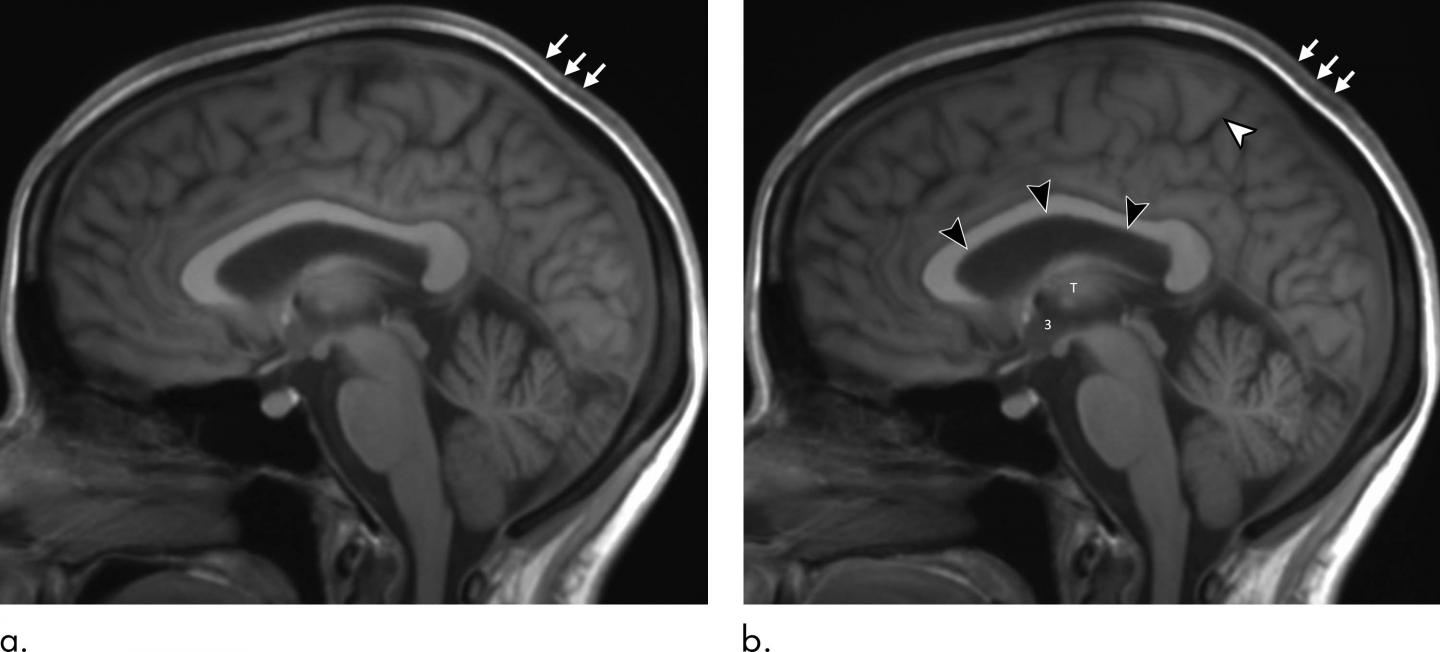

MRI results showed that the long-duration microgravity exposure caused expansions in the astronauts' combined brain and cerebrospinal fluid (CSF) volumes. CSF is the fluid that flows in and around the hollow spaces of the brain and spinal cord. The combined volumes remained elevated at one-year postflight, suggesting permanent alteration.

MRI also showed alterations to the pituitary gland, a pea-sized structure at the base of the skull often referred to as the "master gland" because it governs the function of many other glands in the body. Most of the astronauts had MRI evidence of pituitary gland deformation suggesting elevated intracranial pressure during spaceflight.

"We found that the pituitary gland loses height and is smaller postflight than it was preflight," Dr. Kramer said. "In addition, the dome of the pituitary gland is predominantly convex in astronauts without prior exposure to microgravity but showed evidence of flattening or concavity postflight. This type of deformation is consistent with exposure to elevated intracranial pressures."

The researchers also observed a postflight increase in volume, on average, in the astronauts' lateral ventricles, spaces in the brain that contain CSF. However, the overall resulting volume would not be considered outside the range of healthy adults. The changes were similar to those that occur in people who have spent long periods of bed rest with their heads tilted slightly downward in research studies simulating headward fluid shift in microgravity.

Additionally, there was increased velocity of CSF flow through the cerebral aqueduct, a narrow channel that connects the ventricles in the brain. A similar phenomenon has been seen in normal pressure hydrocephalus, a condition in which the ventricles in the brain are abnormally enlarged. Symptoms of this condition include difficulty walking, bladder control problems and dementia. To date, these symptoms have not been reported in astronauts after space travel.